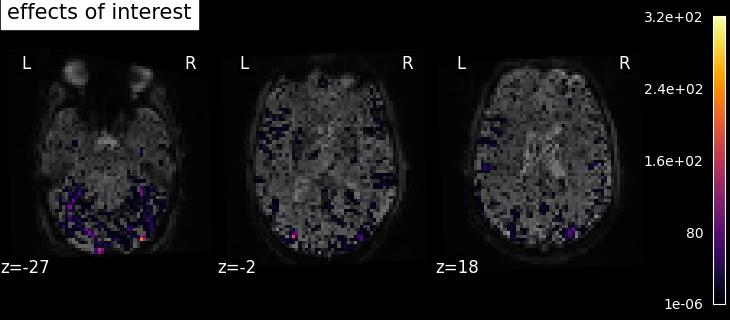

8.2.3.1. Computing contrasts¶

To get more interesting results out of the GLM model, contrasts can be computed between regressors of interest.

The nilearn.glm.first_level.FirstLevelModel.compute_contrast function can be used for that. First,

the contrasts of interest must be defined. In the spm_multimodal_fmri dataset referenced above, subjects are

presented with ‘normal’ and ‘scrambled’ faces. The basic contrasts that can be constructed are the main effects

of ‘normal faces’ and ‘scrambled faces’. Once the basic_contrasts have been set up, we can construct more

interesting contrasts like ‘normal faces - scrambled faces’.

And finally we can compute the contrasts using the compute_contrast function. Refer to Single-subject data (two runs) in native space for the full example.

The activation maps from these 3 contrasts is presented below: